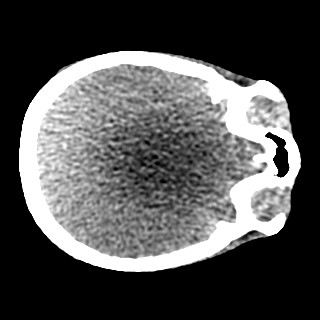

Cone-beam CT (CBCT) employs a flat-panel detector to achieve three-dimensional imaging with high spatial resolution. However, CBCT is susceptible to scatter during data acquisition, which introduces CT value bias and reduced tissue contrast in the reconstructed images, ultimately degrading diagnostic accuracy. To address this issue, we propose a deep learning-based scatter artifact correction method inspired by physical prior knowledge. Leveraging the fact that the observed point scatter probability density distribution exhibits rotational symmetry in the projection domain. The method uses Gaussian Radial Basis Functions (RBF) to model the point scatter function and embeds it into the Kolmogorov-Arnold Networks (KAN) layer, which provides efficient nonlinear mapping capabilities for learning high-dimensional scatter features. By incorporating the physical characteristics of the scattered photon distribution together with the complex function mapping capacity of KAN, the model improves its ability to accurately represent scatter. The effectiveness of the method is validated through both synthetic and real-scan experiments. Experimental results show that the model can effectively correct the scatter artifacts in the reconstructed images and is superior to the current methods in terms of quantitative metrics.